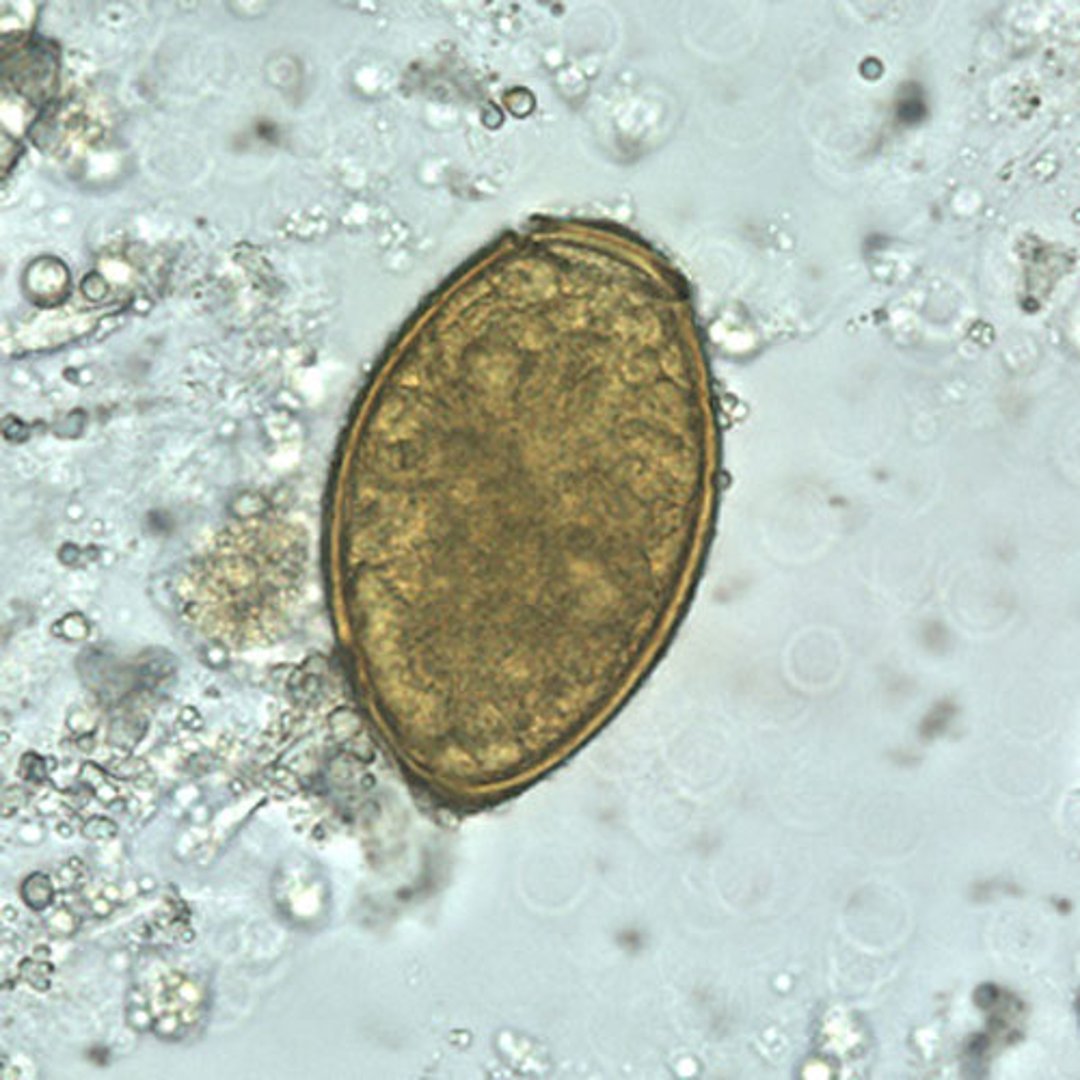

Paragonimus westermani Egg

P. westermani eggs range from 80 to 120 micrometers long by 45 to 70 micrometers wide. They are yellow-brown, ovoid or elongate, and have a thick shell. The eggs are often asymmetrical with one end slightly flattened. At the large end, the operculum is clearly visible. The abopercular end is thickened.

The eggs are unembryonated when passed in sputum or feces.